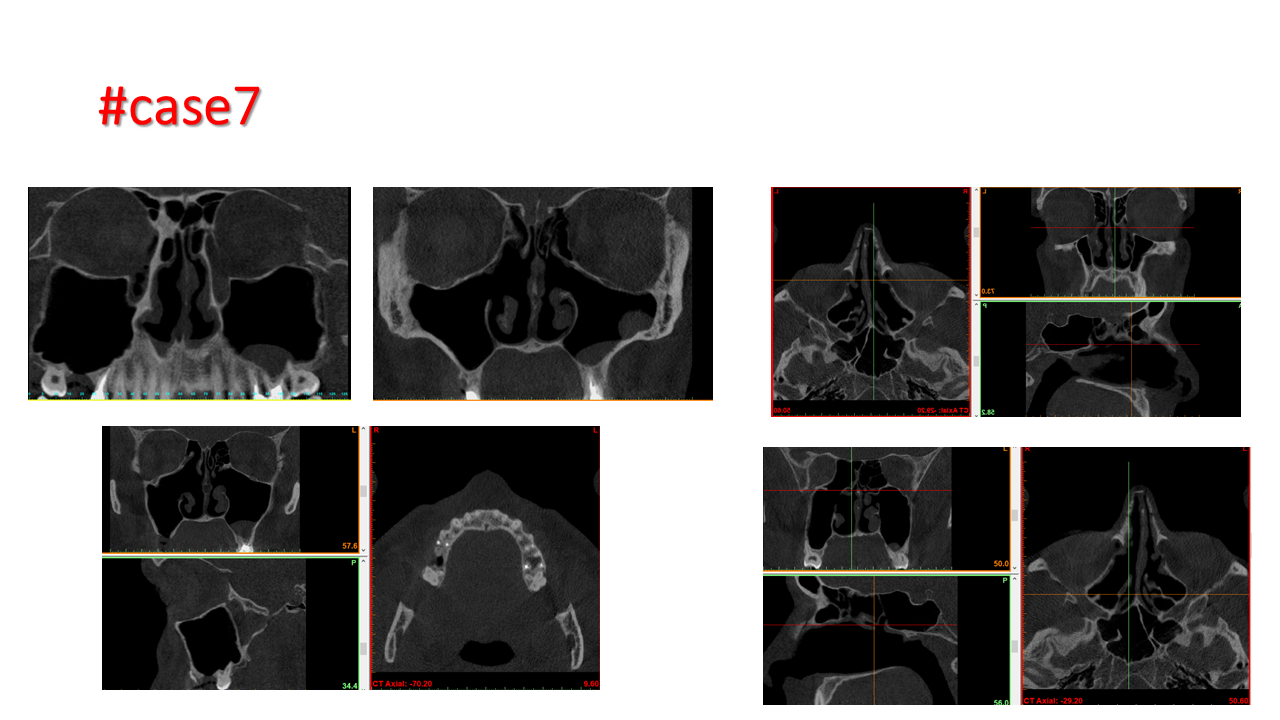

FESS Case Review and Radiologic Analysis (30.09.2016)

Case-based presentation focused on pre- and postoperative imaging in functional endoscopic sinus surgery (FESS). Includes anatomical landmarks, surgical variations, sinus pathology, and technique evaluation. Delivered by Dr. Levon Galstyan at AAOMFS.